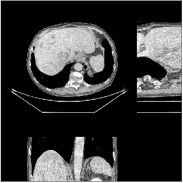

We evaluate the behavior of the PWLS-ULTRA method (with ) for 3D cone-beam CT data with . Fig.Β 2 shows the central slices along three directions for the underlying (true) XCAT phantom volume. We reconstruct the volume from low-dose CT measurements. Fig.Β 2 shows the RMSE and SSIM of PWLS-ULTRA for various choices of , the number of clusters (patch size and patch stride ). Rich models (large ) produce better reconstructions compared to using a single ST (). For the piece-wise constant phantom, clusters works well enough, with only a small additional RMSE or SSIM improvement observed for larger . Larger values of led to sharper image edges.

Fig.Β 5 shows the reconstructions and the corresponding error (magnitudes) images (shown for the central axial, sagittal, and coronal planes) for FDK, PWLS-EP, and PWLS-ULTRA () with the patch-based weights. Compared to FDK and PWLS-EP, PWLS-ULTRA significantly improves image quality by reducing noise and preserving structural details (see zoom-ins). Fig.Β 6 shows the RMSE for each axial slice in the PWLS-EP and PWLS-ULTRA (with the weights ) reconstructions. PWLS-ULTRA clearly provides large improvements in RMSE for many slices, with greater improvements near the central slice.